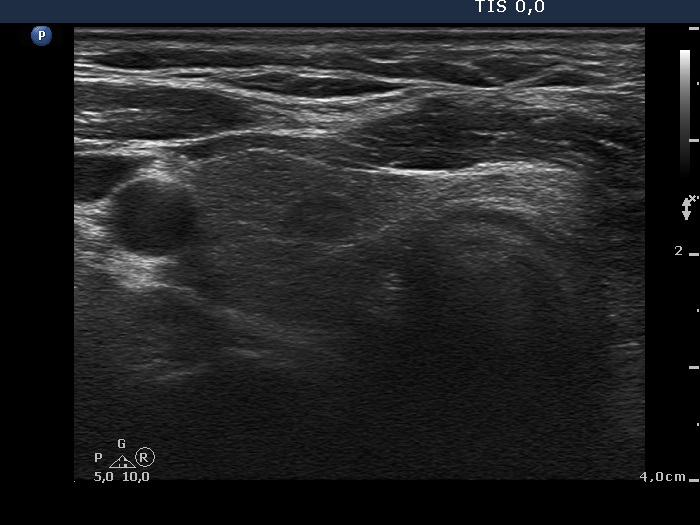

Six weeks after surgery (first row of images):

Clinical data: A 38-year-old woman underwent on near total left lobectomy because of follicular adenoma 6 weeks ago.

Palpation: no abnormality.

Result of blood test: euthyroidism with a minimally elevated TSH level (TSH 4.51 mIU/L, FT4 14.0 pM/L).

Ultrasonography. The right lobe was echonormal and had a small, insignificant lesion. According to the left thyroid, there was an inhomogeneous mass corresponding to regenerative tissue. The mass was not well-demarcated.